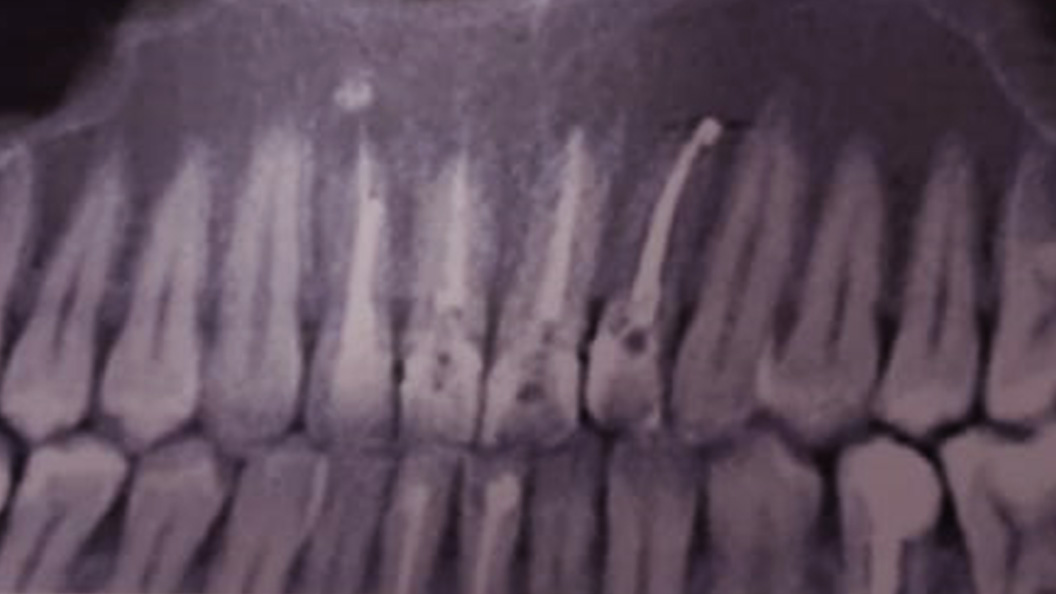

До и после лечения

Пациентка обратилась в «Стоматологию Комфорта» с жалобами на периодические ноющие боли в зубе 1.2. Врач Тарасов Денис Геннадьевич провёл обследование и поставил диагноз — хронический периодонтит верхнего резца. Проведено удаление зуба с одномоментной имплантацией.